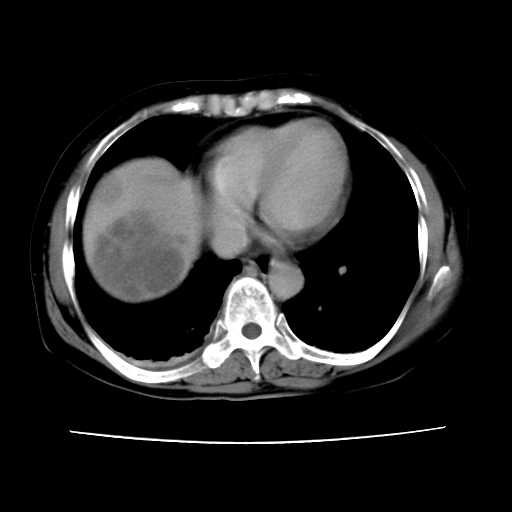

2008-6-10ct平扫

ct增强

6月片:肝血管瘤并破裂出血?肝左外叶囊肿

考虑肝腺瘤出血可能,肝血管瘤增强表现不是很典型,放在第二。

考虑为肝血管瘤破裂出血并肝包膜下血肿;右侧少量胸腔积液。

6月份ct片显示肝内巨大混杂密度团块,伴包膜下积液(内含液液平面),增强多无明显强化。只能考虑肝占位病变,并肝内、血膜下血肿。肝ca并出血多见,而肝血管瘤并破裂出血少见。